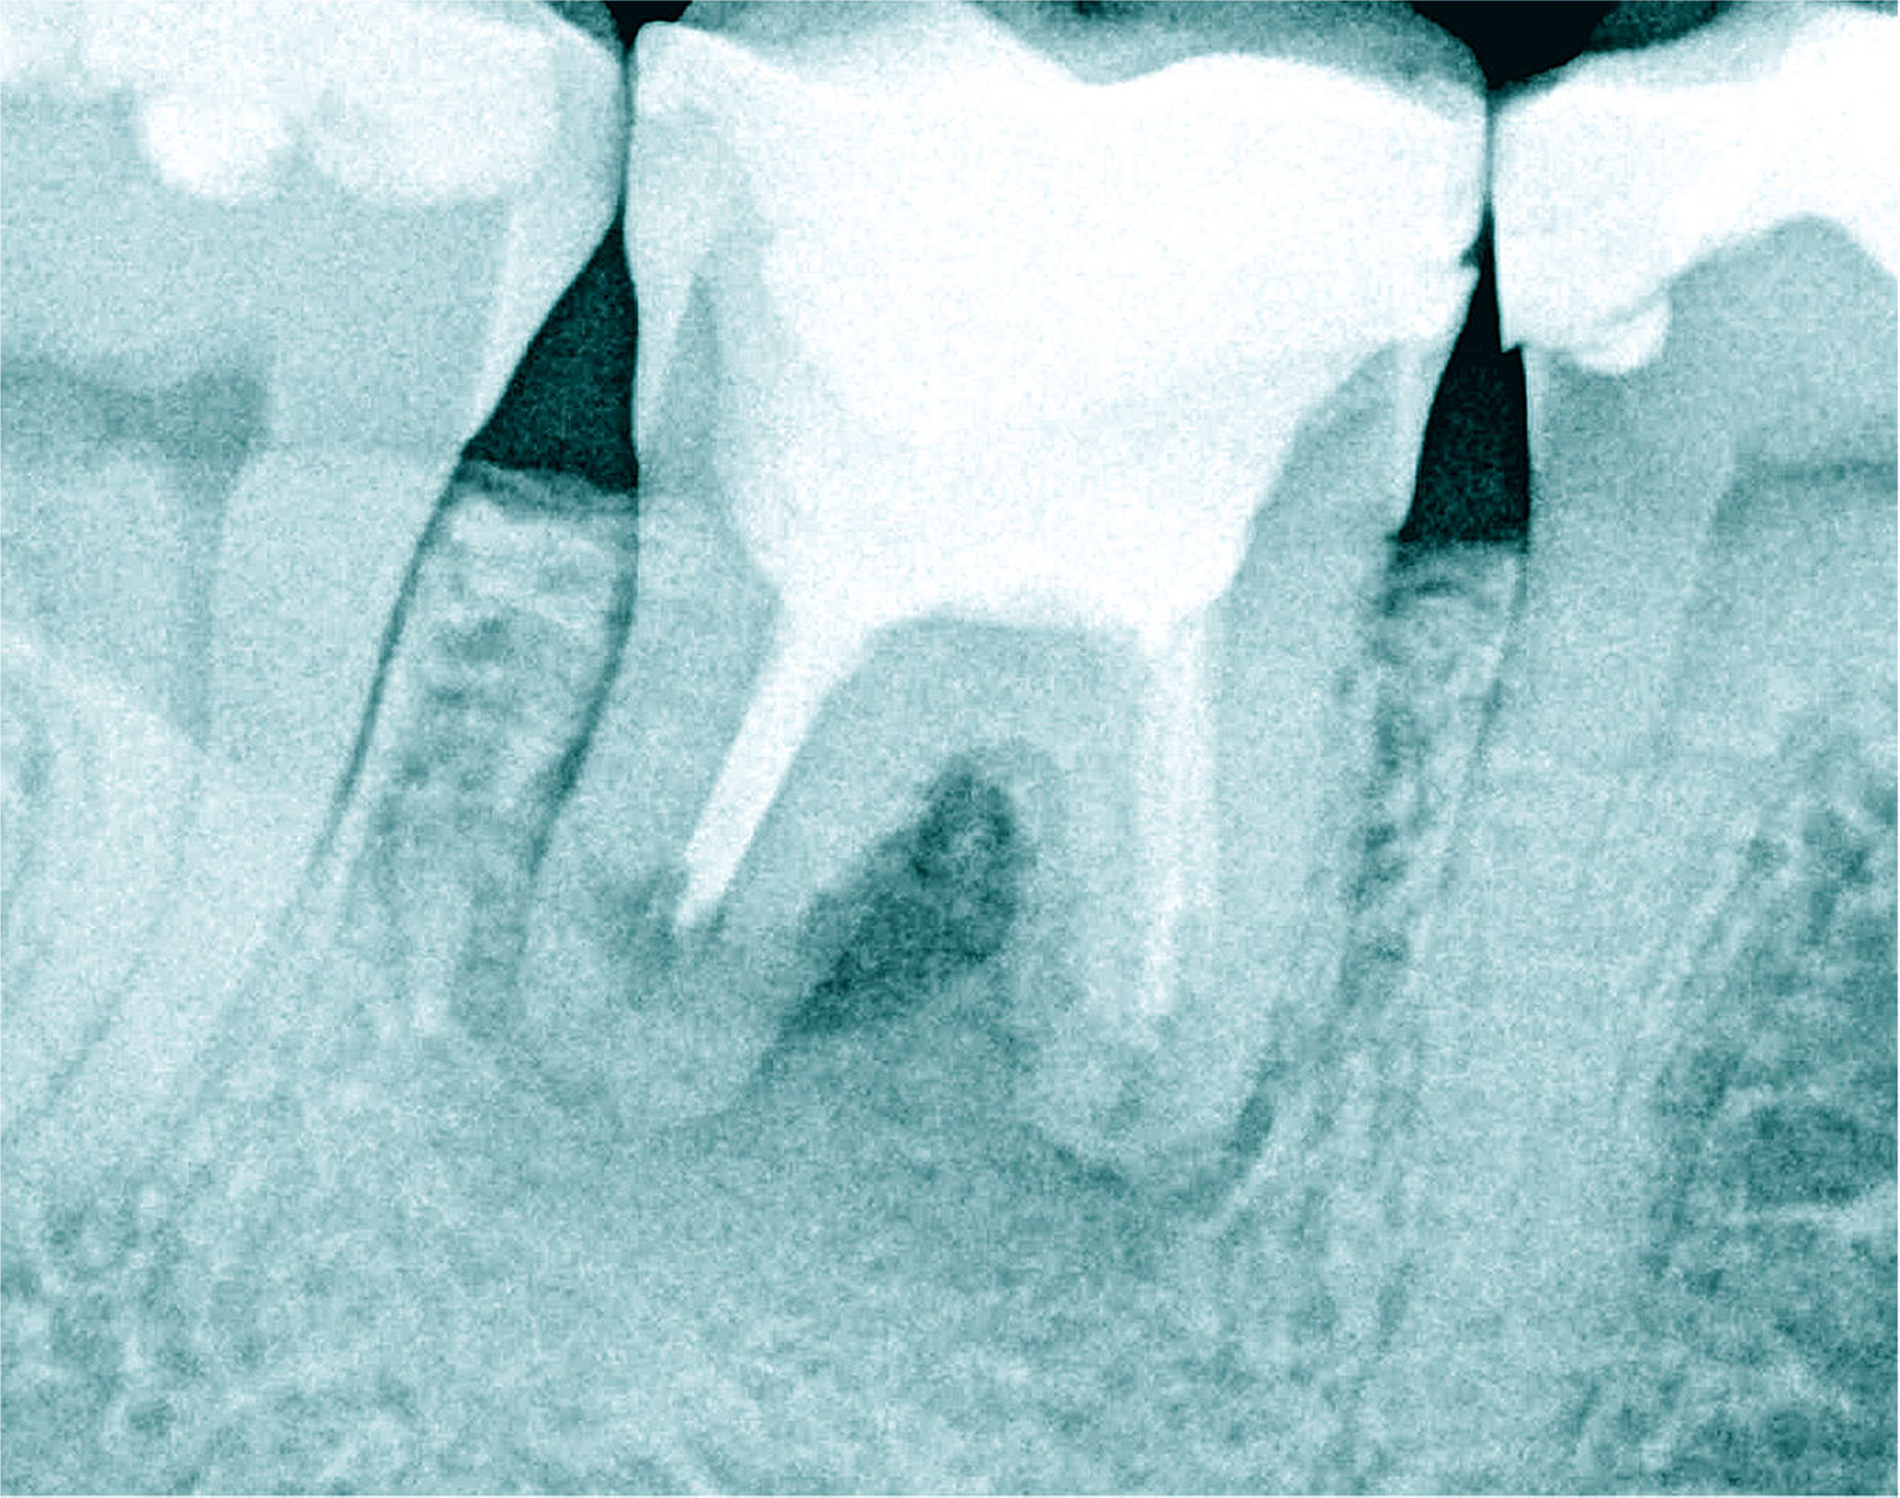

Der Patient stellte sich mit rezidivierenden Beschwerden am Zahn 45 nach einer vor Jahren abgeschlossenen Wurzelkanalbehandlung vor. Die Allgemeinanamnese war unauffällig. Die Schmerzsymptomatik ließ sich auf den Zahn 45 bei positivem Perkussionsreiz lokalisieren. Der approximale Kontaktpunkt distal zum Zahn 46 fehlte. Distal fiel ein pathologischer Sondierungswert von 4 mm auf. Eine Blutung ließ sich bei passiver Messung auslösen und begründete eine plaqueinduzierte Gingivitis.

Auf der intraoralen Röntgenaufnahme lagen eine unvollständige Wurzelkanalfüllung und eine apikale Aufhellung am Zahn 45 vor. Apikal ist auf der Röntgenaufnahme kein Wurzelkanal erkennbar. Die zu kurze Wurzelkanalfüllung deutete auf eine apikale Blockade von eingepresstem Debris oder eine Stufenpräparation hin (Abbildung 14). Als seltene anatomische Variation war eine apikale Aufteilung in zwei Wurzelkanäle in Betracht zu ziehen, so dass die Nutzung einer optischen Vergrößerung mit koaxialer Lichtzufuhr als Hilfsmittel empfehlenswert erschien. Die apikale Wurzelkrümmung ließ einen gleichmäßigen großen Krümmungsradius vermuten. Bei lateralen Aufhellungen ist mit einem lateralen Foramen apicale oder einer Wurzelkanalaufteilung zu rechnen, so dass in diesem Fall die apikale Erweiterung und der Verschluss eine sehr hohe Schwierigkeit vermuten lassen.

Die Differenzialdiagnostik und die Therapie unterlagen erwartungsgemäß dem sehr hohen Schwierigkeitsgrad. Es wurde eine dentinadhäsive Aufbaufüllung mit Restauration des fehlenden Kontaktpunkts bei subgingivaler Lage des Füllungsrandes erforderlich und zusätzlich musste die apikale Blockade minimalinvasiv mit modernen endodontischen Hilfsmitteln eliminiert werden. Die Entfernung der alten Wurzelkanalfüllung gelang in der Kombination von Handinstrumenten und rotierenden NiTi-Feilen (Abbildungen 15a und 15b). Unter Sicht mit dem Dentalmikroskop konnte die intrakanaläre Blockade mit Ultraschall und vorgebogenen Feilen überwunden und thermoplastisch verschlossen werden, so dass bereits sechs Monate nach Therapieabschluss die apikale Aufhellung und klinische Schmerzsymptomatik abgeklungen waren (Abbildung 15c).